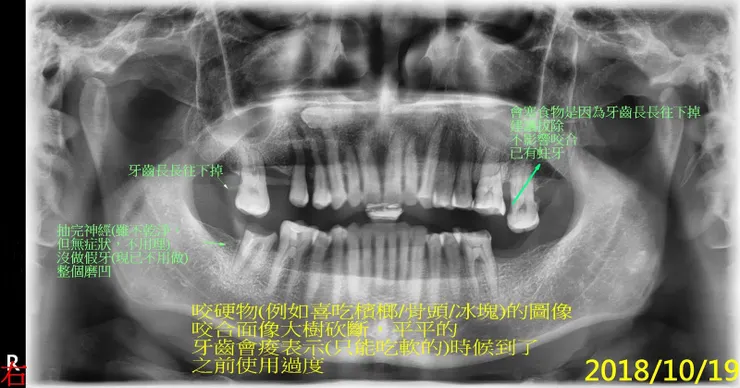

常有人好奇磨牙會怎麼磨掉牙齒?剛好有個適當的例子做說明。

接下來是比較精采,喔,不,警世的例子,說明為何我要幫每一個新病人照x光片。